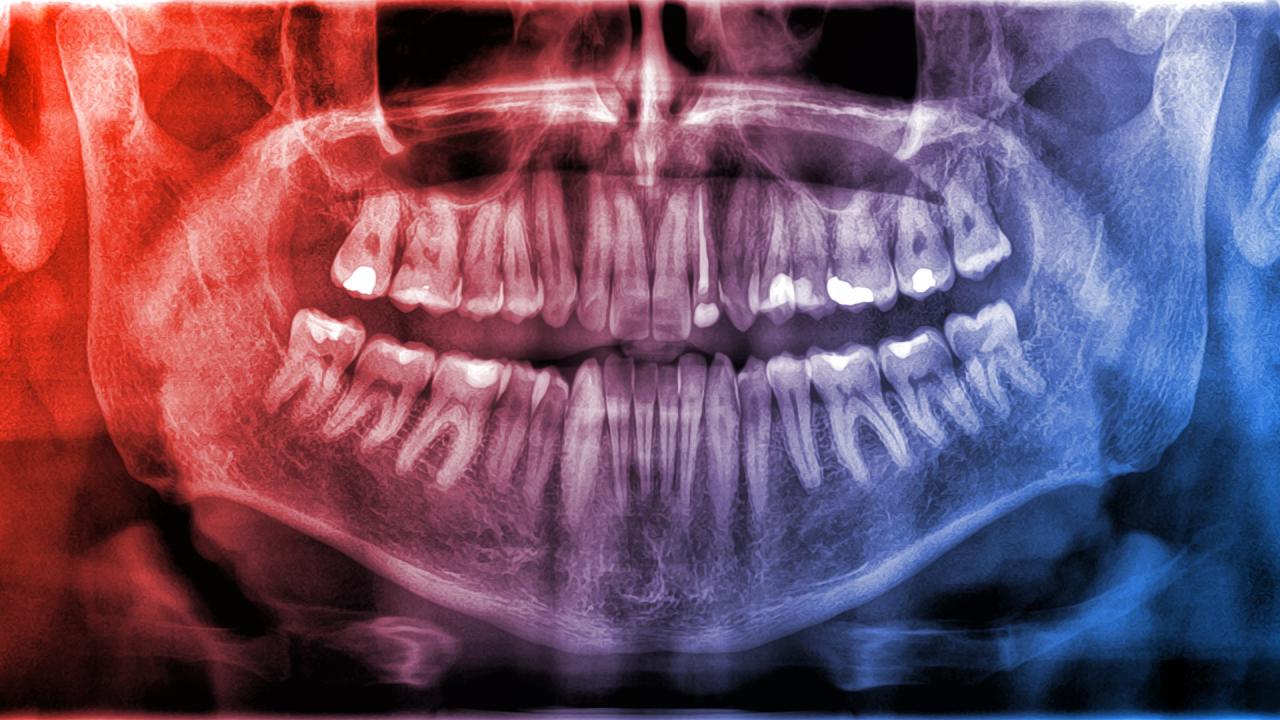

A fogak kívülről egy vékony zománcréteggel rendelkeznek, amely a test legkeményebb anyaga. A zománc alatt dentinréteg található, amely valamivel puhább, de még mindig kemény, és apró csövek hálózzák be, bennük idegvégződésekkel és hajszálerekkel. A fog belsejében található a puha, zselészerű pulpa, itt futnak össze nagyobb vérerek és idegek.

Ugyanakkor a csontok felépítése más: kívülről egy kemény, vékony, periosteumnak nevezett réteg borítja, amely szintén tartalmaz ereket és idegeket. Alatta helyezkedik el a masszív kompakt állomány, a csont belseje pedig szivacsos állományt rejt, melyben – főként a nagyobb csöves csontokban – a csontvelő található, ahol a vérsejtek képződnek.